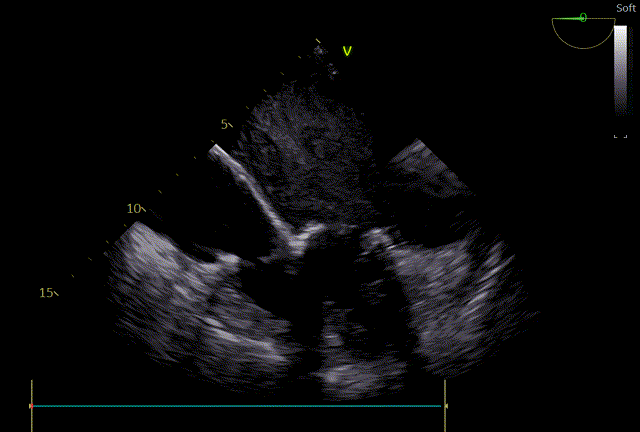

心脏超声示:风湿性心脏病、二尖瓣狭窄(重度)并反流(中度)、三尖瓣反流(重度)、肺动脉高压(重度)、主动脉瓣反流(轻度)。二尖瓣前后叶瓣尖增厚、钙化、粘连、开放受限、瓣下腱索挛缩。2D测MVA:0.8 cm²,PHT法测为:0.8cm²。瓣环前后径32mm,左右径32 mm。CDFI:收缩期二尖瓣房侧见中量反流信号,反流束面积5.6cm²。收缩期三尖瓣房侧见大量反流信号,反流束面积10.5cm²,TRVmax:457cm/s,PG:83 mHg,TI法估测SPAP:93 mmHg。心律不齐。

术后即时食道超声示:二尖瓣未见瓣周漏,生物瓣功能良好,三尖瓣未见明显返流。

术后床旁超声描述:MVR+TVP术后,双房增大。二尖瓣位为人工生物瓣回声,瓣环位置固定,瓣叶活动良好,未见赘生物回声。PHT法测二尖瓣人工生物瓣口面积:3.8cm²,三尖瓣见成形环强回声,CDFI:未见异常。